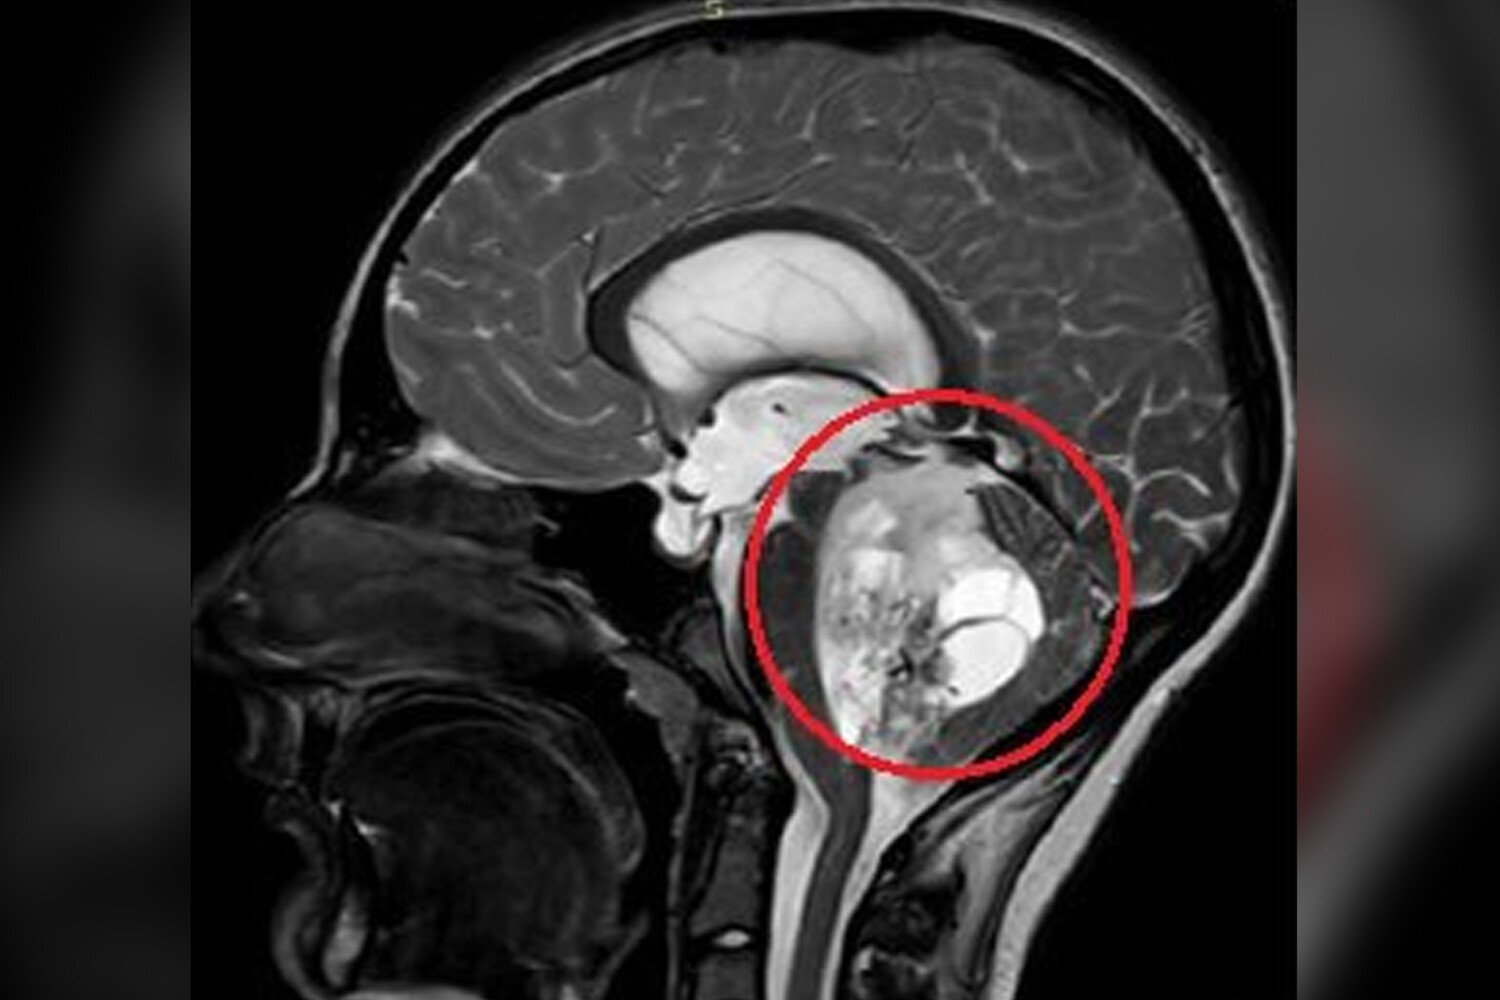

По словам медиков, юноша жаловался на постоянную тошноту и рвоту, которые не удавалось купировать консервативными методами. На обследовании специалисты обнаружили пятисантиметровую опухоль в задней черепной ямке. По словам врачей, ее дальнейший рост мог привести к нарушению жизненно важных функций мальчика.

«Сложность данного случая заключалась в том, что опухоль росла из области, которая отвечает за жизненно важные функции - любое, даже маленькое повреждение могли привести к тяжелым неврологическим осложнениям», — отметили нейрохирурги.